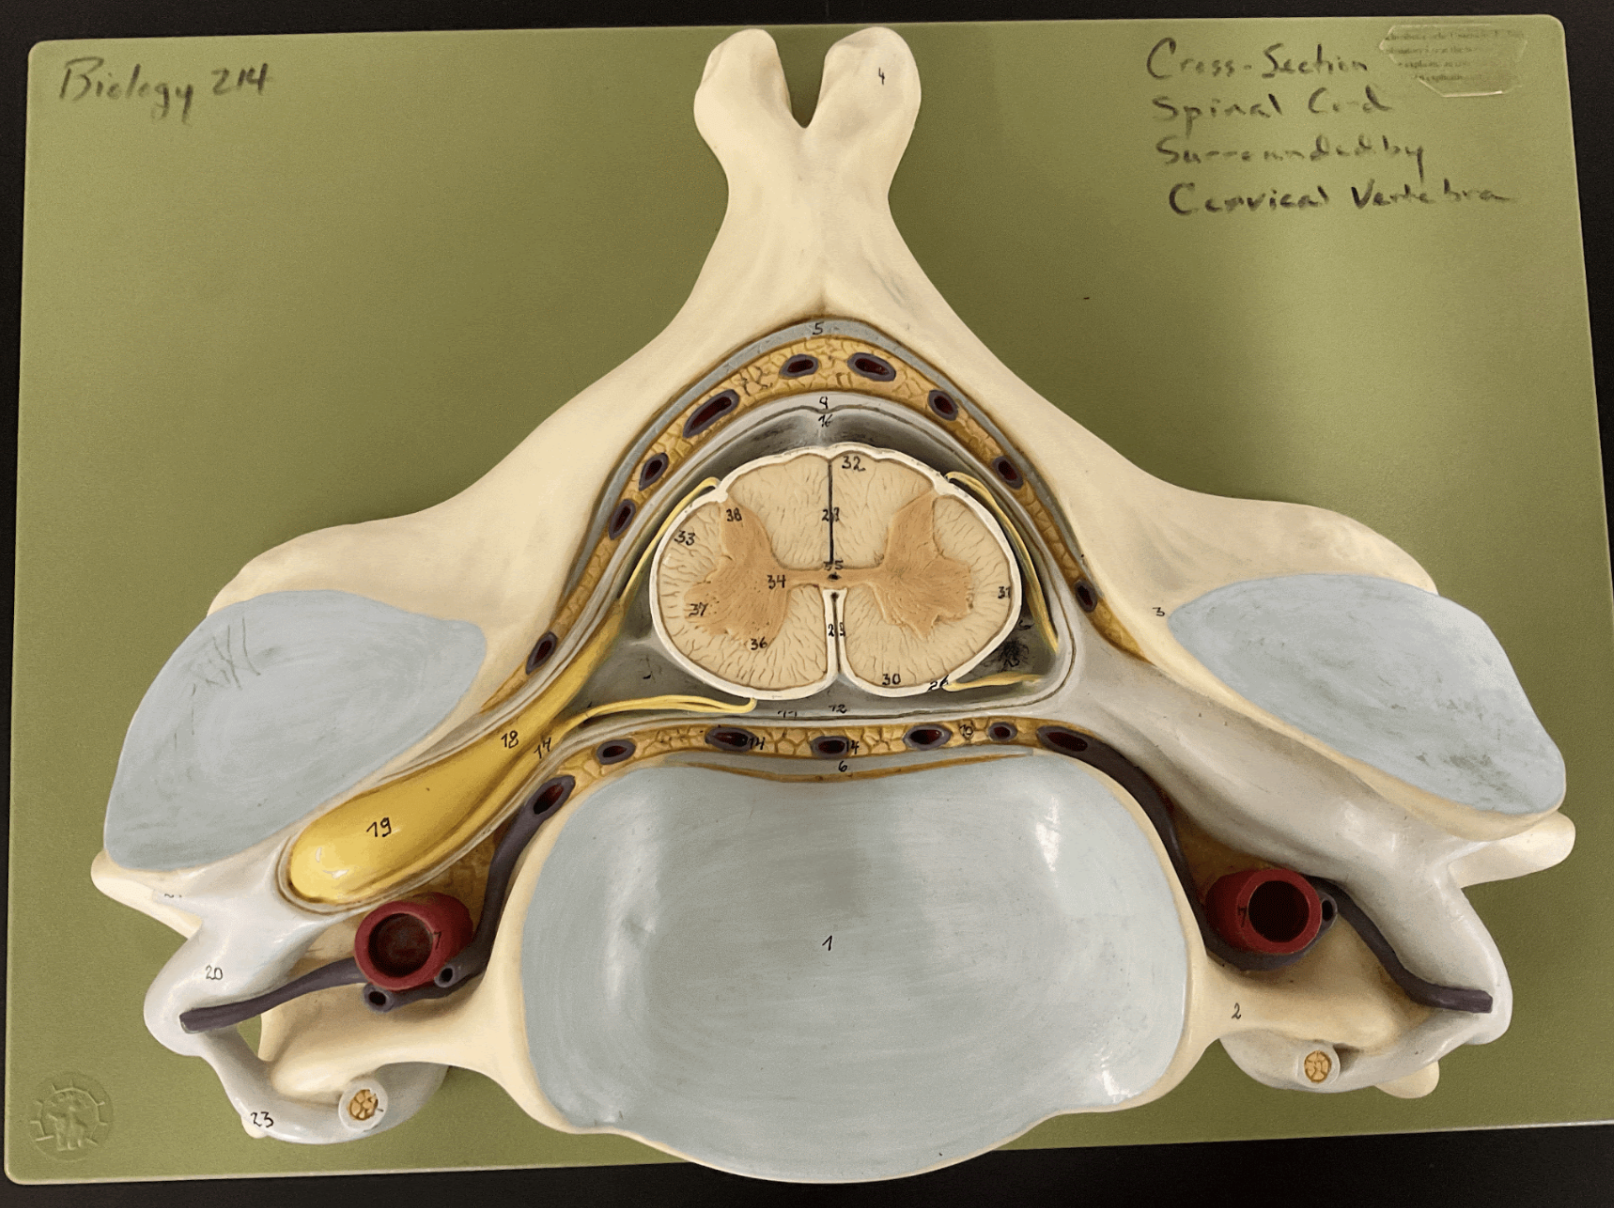

dura mater

9

arachnoid mater

12

pia mater

24, outside of white matter

epidural space

10, outside of dura mater

subdural space

yellow orange line

subarachnoid space

13, outside pia mater

posterior root

18

posterior root ganglion

19

posterior ramus

21

anterior root

17

anterior ramus

20